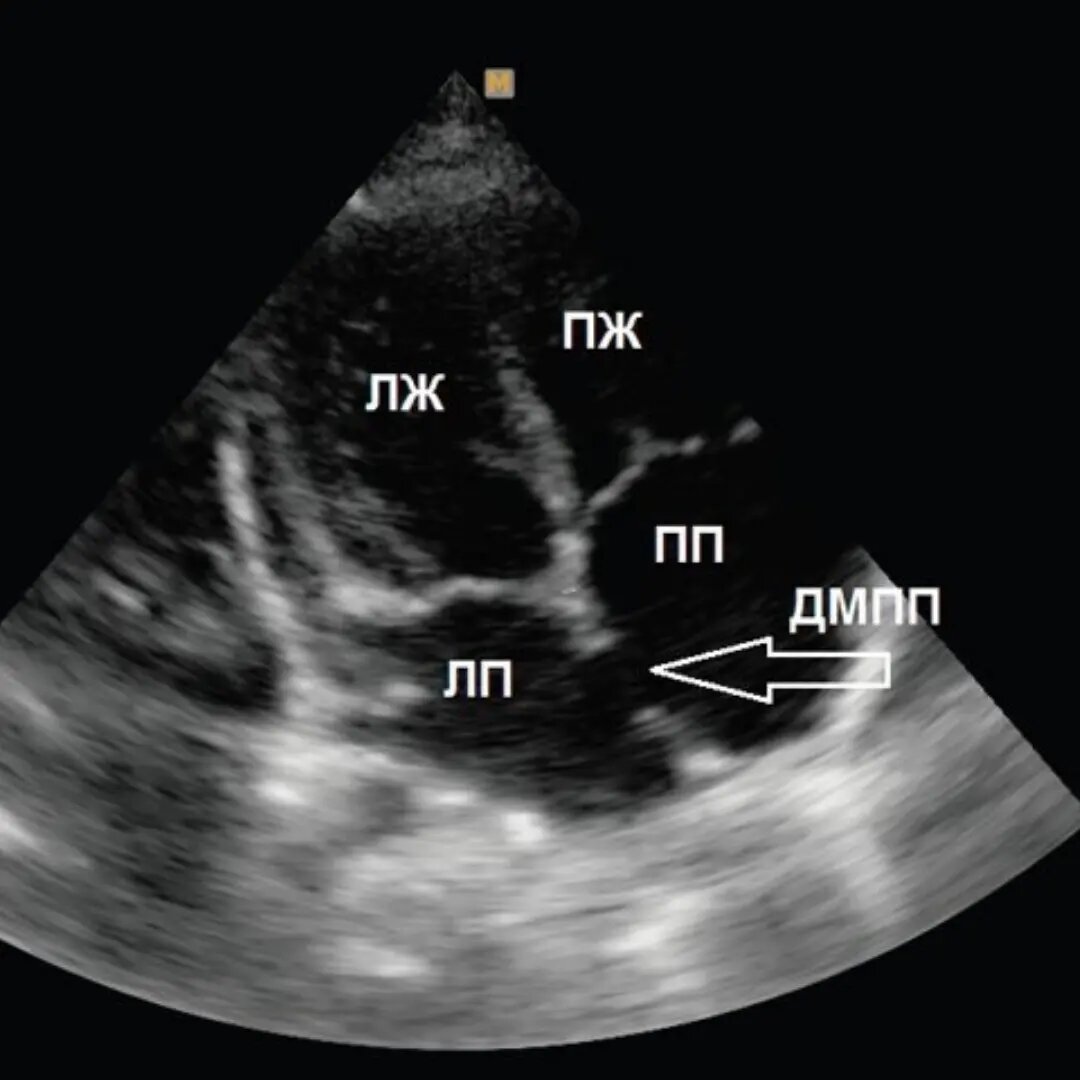

Дефект межпредсердной перегородки.

Дефект межпредсердной перегородки (ДМПП) - отверстие в перегородке между правым и левым предсердиями, приводящее к шунтированию крови слева направо, что может приводить к перегрузке объемом правых отделов сердца. Это распространённый порок сердца, составляет примерно 6–10% случаев врождённых пороков сердца. Большинство случаев отдельные и спорадические, но некоторые являются частью генетического синдрома. ДМПП можно классифицировать по местоположению: 🔸Ostium secundum - дефект в овальной ямке – в центральной части межпредсердной перегородки. Самый частый из ДМПП, его следует отличать от открытого овального окна: вскоре после рождения оно обычно зарастает. В случае же дефекта речь идет об отсутствии ткани межпредсердной перегородки. 🔸Sinus venosus - располагаются в верхнем отделе МПП, вблизи места впадения верхней полой вены, в этой же области часто обнаруживается и аномальное впадение правых лёгочных вен. 🔸Ostium primum - располагается в самом низу межпредсердной перегородки, над

С помощью последнего метода можно определить анатомическое расположение и размер дефекта, а также оценить степень перегрузки объемом правого предсердия и правого желудочка.